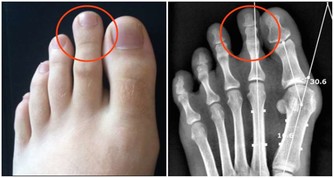

⑥定期檢查。時不時地就自己觀察身體有沒有變化,而且不管身體如何,每年都要做體檢,及時知道身體狀況。